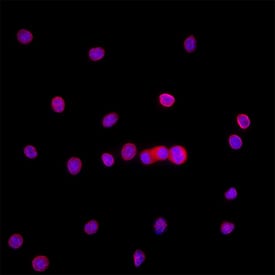

Detection of Ki67/MKI67 in Raw264.7.

Ki67/MKI67 was detected in immersion fixed RAW264.7 cells using Mouse Anti-Mouse Ki67/MKI67 Monoclonal Antibody (Catalog # MAB11612) at 8 µg/ml for 3 hours at room temperature. Cells were stained using the NorthernLights™ 557-conjugated Anti-Rat IgG Secondary Antibody (red; Catalog # NL013) and counterstained with DAPI (blue). Specific staining was localized to the nucleus. View our protocol for Fluorescent ICC Staining of Cells on Coverslips.